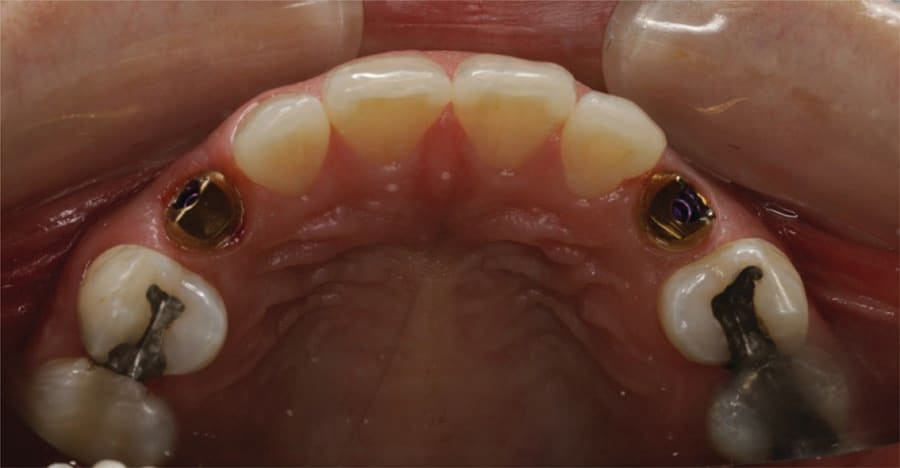

The patient returned and the healing abutments were removed. The gold-plated custom abutments from Atlantis were inserted, and the screw was hand tightened (Figure 18 and Figure 19). A radiograph was taken to verify the complete mating of the abutments with the implant’s connector. The screw was tightened to 25 ncm with a torque wrench. A piece of PTFE tape was placed into the screw access channel of the abutment and the provisional crowns were tried in. Fit and occlusion were verified. The provisional crowns were cemented to the abutment with Temp-Bond (Kerr Dental). Following setting of the cement the restoration margins were cleaned with an instrument to remove any residual cement. The occlusion was checked and the patient dismissed. The patient will wear the provisional crowns for a period of time to allow the gingival tissue to adapt to the crown’s contours before fabrication of the final crowns.